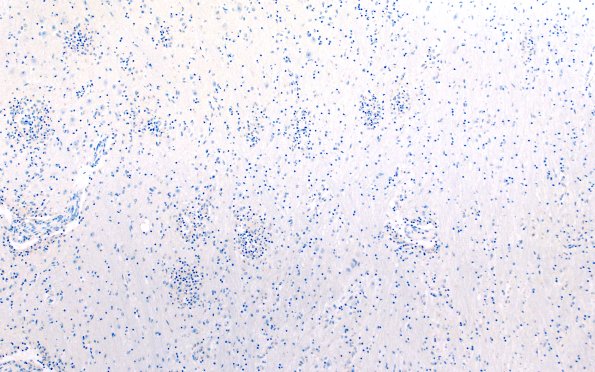

Washington University Experience | MISCELLANEOUS | Familial erythrophagic lymphohistiocytosis | 4D Lymphohistiocytosis (Case 4) CD20 N3 10X

B cells were essentially absent from the perivascular or parenchymal infiltrates. (CD20 IHC)